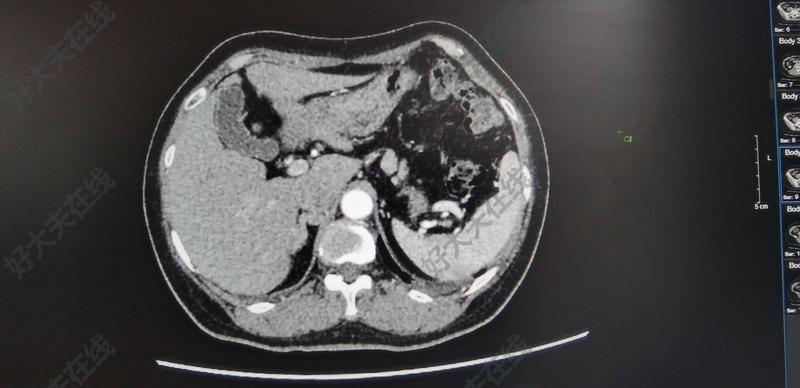

治療前這個患者有高血壓多年的病史,同時合并有低鉀血癥,屬于比較典型的醛固酮增多癥的癥狀,曾經(jīng)在外院做了醛固酮的檢驗,考慮原發(fā)性醛固酮增多癥可能性比較大,進(jìn)一步檢查了卡托普利抑制實驗和腎上腺靜脈靜脈取血,但是由于當(dāng)?shù)氐募夹g(shù)限制,并有能夠完全明確優(yōu)勢側(cè)治療中通過仔細(xì)研究患者外院的抑制實驗結(jié)果和腎上腺靜脈分段取血的結(jié)果,再結(jié)合再結(jié)合CT的檢查,我們基本上還是可以通過謹(jǐn)慎的邏輯推斷,確認(rèn)患者屬于右側(cè)腎上腺優(yōu)勢側(cè),同時仔細(xì)閱讀CT,那在這個腔靜脈的后方找到了高度疑似的醛固酮瘤,我們通過與患者詳細(xì)的溝通,最終還是達(dá)成了一致,選擇了腹腔鏡下的右側(cè)腎上腺切除術(shù)治療后治療后1天術(shù)后患者癥狀明顯緩解,血醛固酮水平恢復(fù)正常,術(shù)后恢復(fù)良好,準(zhǔn)備明日出院

近日,一位老年,73歲,女性患者因右腎上腺腺瘤來我院就診。CT示:經(jīng)完善檢查,診斷為:原發(fā)性醛固酮增多癥。患者既往合并多種內(nèi)科疾病:1、高血壓3級,2、2型糖尿病,3、冠心病,4、支氣管哮喘,5、低鉀血癥,6、低蛋白血癥。因為合并多種內(nèi)科病,所以患者非常慎重和擔(dān)心,疑慮重重。經(jīng)過與患者及家屬詳細(xì)分析病情,溝通手術(shù)及圍手術(shù)期的護(hù)理與治療,最終打消了患者的顧慮。于近日行腹腔鏡下腎上腺腺瘤切除術(shù)。在心內(nèi)科,呼吸科,手麻科的通力配合下,手術(shù)很順利成功,用時40分鐘?;颊吣壳耙讶鲈?。